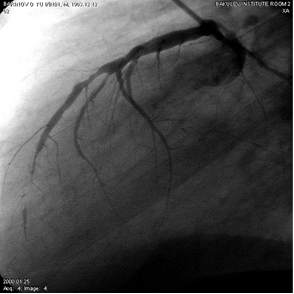

Первичный отбор больных ИБС, рефрактерных к медикаментозной терапии, на операцию ТМЛР осуществлялся по данным коронарографии. Основанием для отбора больных на ТМЛР явилась идентификация множественного поражения коронарных артерий в виде “четок” (рис. 3), диффузного поражения КА с выраженным сужением просвета, либо с полным его закрытием, когда просвет сосуда представлен непроходимыми тяжами, перемежающимися с ”островками” бывшего коронарного русла, заполненного контрастным веществом через коллатерали (рис 4).

Рис. 3. Коронарограмма больного П., 58 лет. Множественные четкообразные поражения ПМЖВ на всем ее протяжении. Видны диффузные изменения ДВ и сосудов системы ОВ